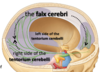

Name areas A-C

Name areas A and B

Name venous structures A-C

Name areas A-C